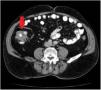

Given those findings, a chest and abdominal CT scan was carried out that described a thickening in an approximately 8 cm segment of the ascending colon, toward the hepatic flexure, with probable involvement of the ileocecal valve, consistent with a primary tumor with no adenopathies, distant disease, or signs of bowel obstruction (Fig. 2).

Radiologically, abdominal CT findings of intestinal tuberculosis include wall thickening of a segment of the intestine, abdominal adenopathies with central necrosis, intra-abdominal collections, or peritoneal inflammation. When there is colorectal involvement, the most frequent findings are strictures, signs of colitis, or polypoid lesions. In such cases, amebic, ischemic, or pseudomembranous colitis, as well as malignant disease, make up the differential diagnosis of colorectal tuberculous involvement. Therefore, diagnosis must be based on a high degree of suspicion and demonstrated by the presence of caseating granulomas in the endoscopic intestinal biopsies,8,9 which is an aspect that differentiates the diagnosis from that of Crohn’s disease, together with a positive smear or culture for acid-resistant bacilli.7,8 However, in some cases, the clinical and endoscopic response to antituberculosis treatment is still needed to make the diagnosis.5,7